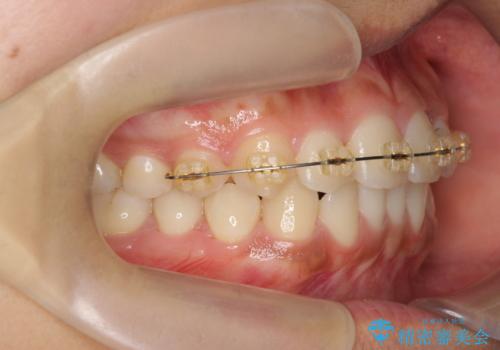

- インビザライン +部分ワイヤー矯正

上顎前歯のみの部分ワイヤー治療を約6ヶ月行い、ねじれの問題を解決したのち、マウスピース矯正で細かな歯列を整えていきます。